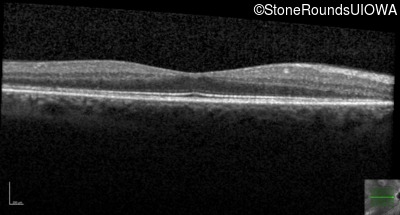

Optical Coherence Tomography - Left - 20/32

Exemplar / OCT Stack